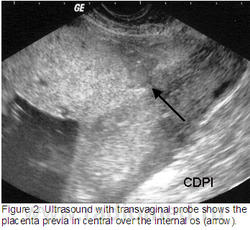

Клиника де Diagnóstico пор Imagem (CDPI), Институт Fernandes Figueira (IFF) - FIOCRUZ